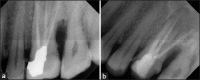

Inappropriate mechanical debridement, persistence of bacteria in the canals and apex, poor obturation quality, over and under extension of the root canal filling, and coronal leakage are some of the commonly attributable causes of failure. Despite the high success rate of endodontic treatment, failures do occur in a large number of cases and most of the times can be attributed to the already stated causes. With an ever increasing number of endodontic treatments being done each day, it has become imperative to avoid or minimize the most fundamental of reasons leading to endodontic failure. This paper reviews the most common causes of endodontic failure along with radiographic examples.